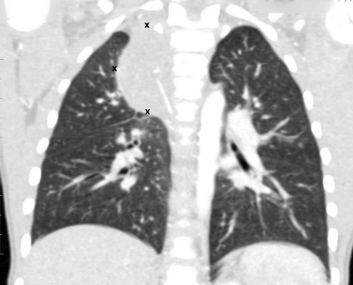

Метастатическое поражение легких